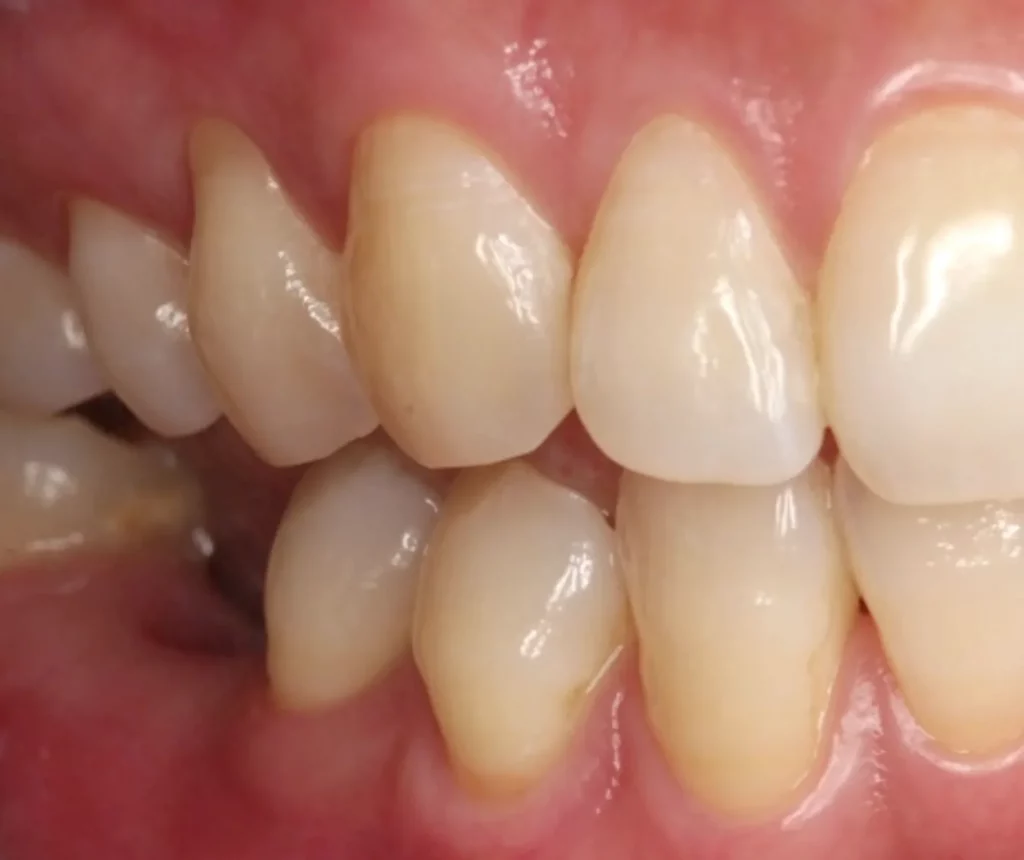

This woman had a badly broken down lower molar that had split apart and had been painfully abscessing for months. Unfortunately, it was beyond saving, and it was extracted. Keen to have the space restored, the patient opted to have an implant placed.

Below shows the crown fitted on to the implant post.